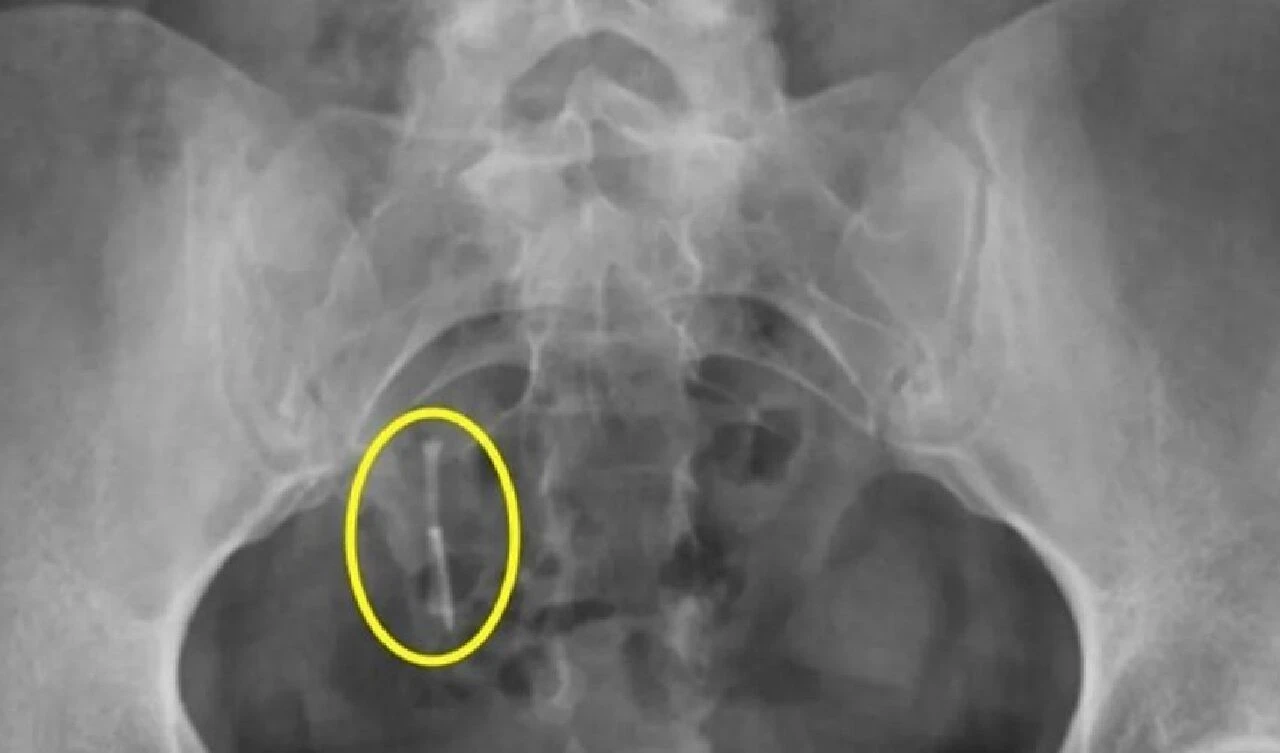

Genç kadın, trafik kazası geçirdikten sonra tetkikler esnasında çekilen röntgende, spiralin kalın bağırsağının içinde olduğu ve rahmini deldiği ortaya çıktı.

Facebook'ta paylaşım yapan Hampton, röntgenlerinin fotoğraflarını "Vücudunuza güvenin hanımlar. Onun içimde olduğunu her zaman biliyordum ama kanıtlayamıyordum" başlığıyla paylaştı.